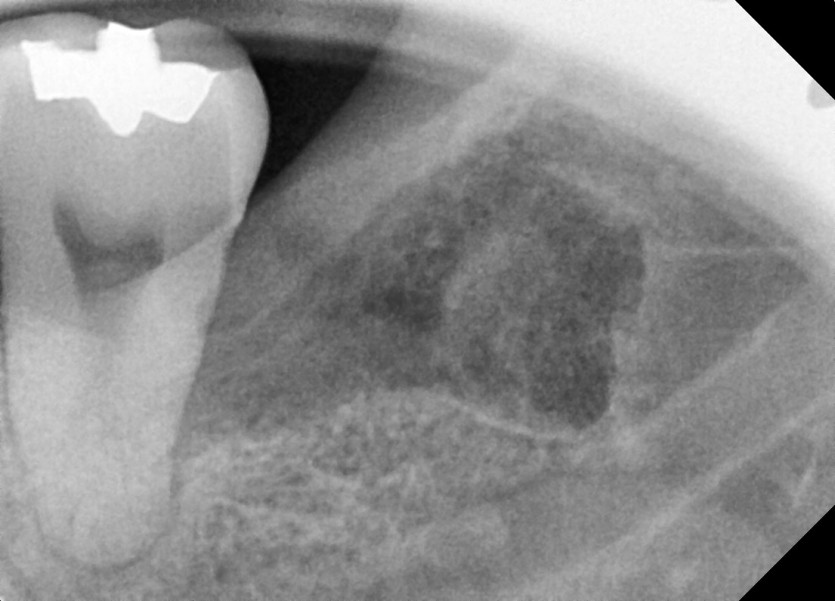

#38 사랑니 발치

구강 외과 전문의가 당일 발치했습니다.